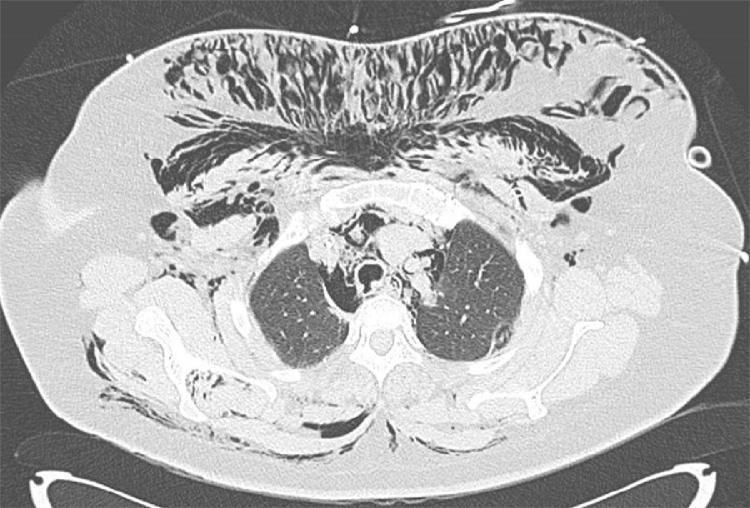

A 39-year-old female underwent an elective laparoscopic adhesiolysis. At the end of the procedure, the patient had developed subcutaneous emphysema. A CT-scan showed mediastinal and subcutaneous emphysema and left pneumothorax with a laceration of the membranous portion of the middle third of the trachea. A left pleural drain was inserted and a bronchoscopy showed a 2-cm long tear of the membranous portion in the middle third of the trachea. Veno-venous ECMO was established and surgical repair of the tracheal lesion was performed. Post-operative recovery was uneventful and the patient was discharged on 8th postoperative day.

一名39岁女性接受了择期腹腔镜粘连松解术。手术结束时,患者出现了皮下气肿。CT扫描显示纵隔和皮下气肿以及左气胸,气管中三分之一膜部有撕裂伤。插入了左胸腔引流管,支气管镜检查显示气管中三分之一膜部有一处2厘米长的撕裂。建立了静脉-静脉ECMO,并对气管损伤进行了手术修复。术后恢复顺利,患者于术后第8天出院。